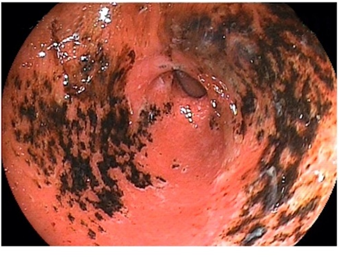

图片

image.png